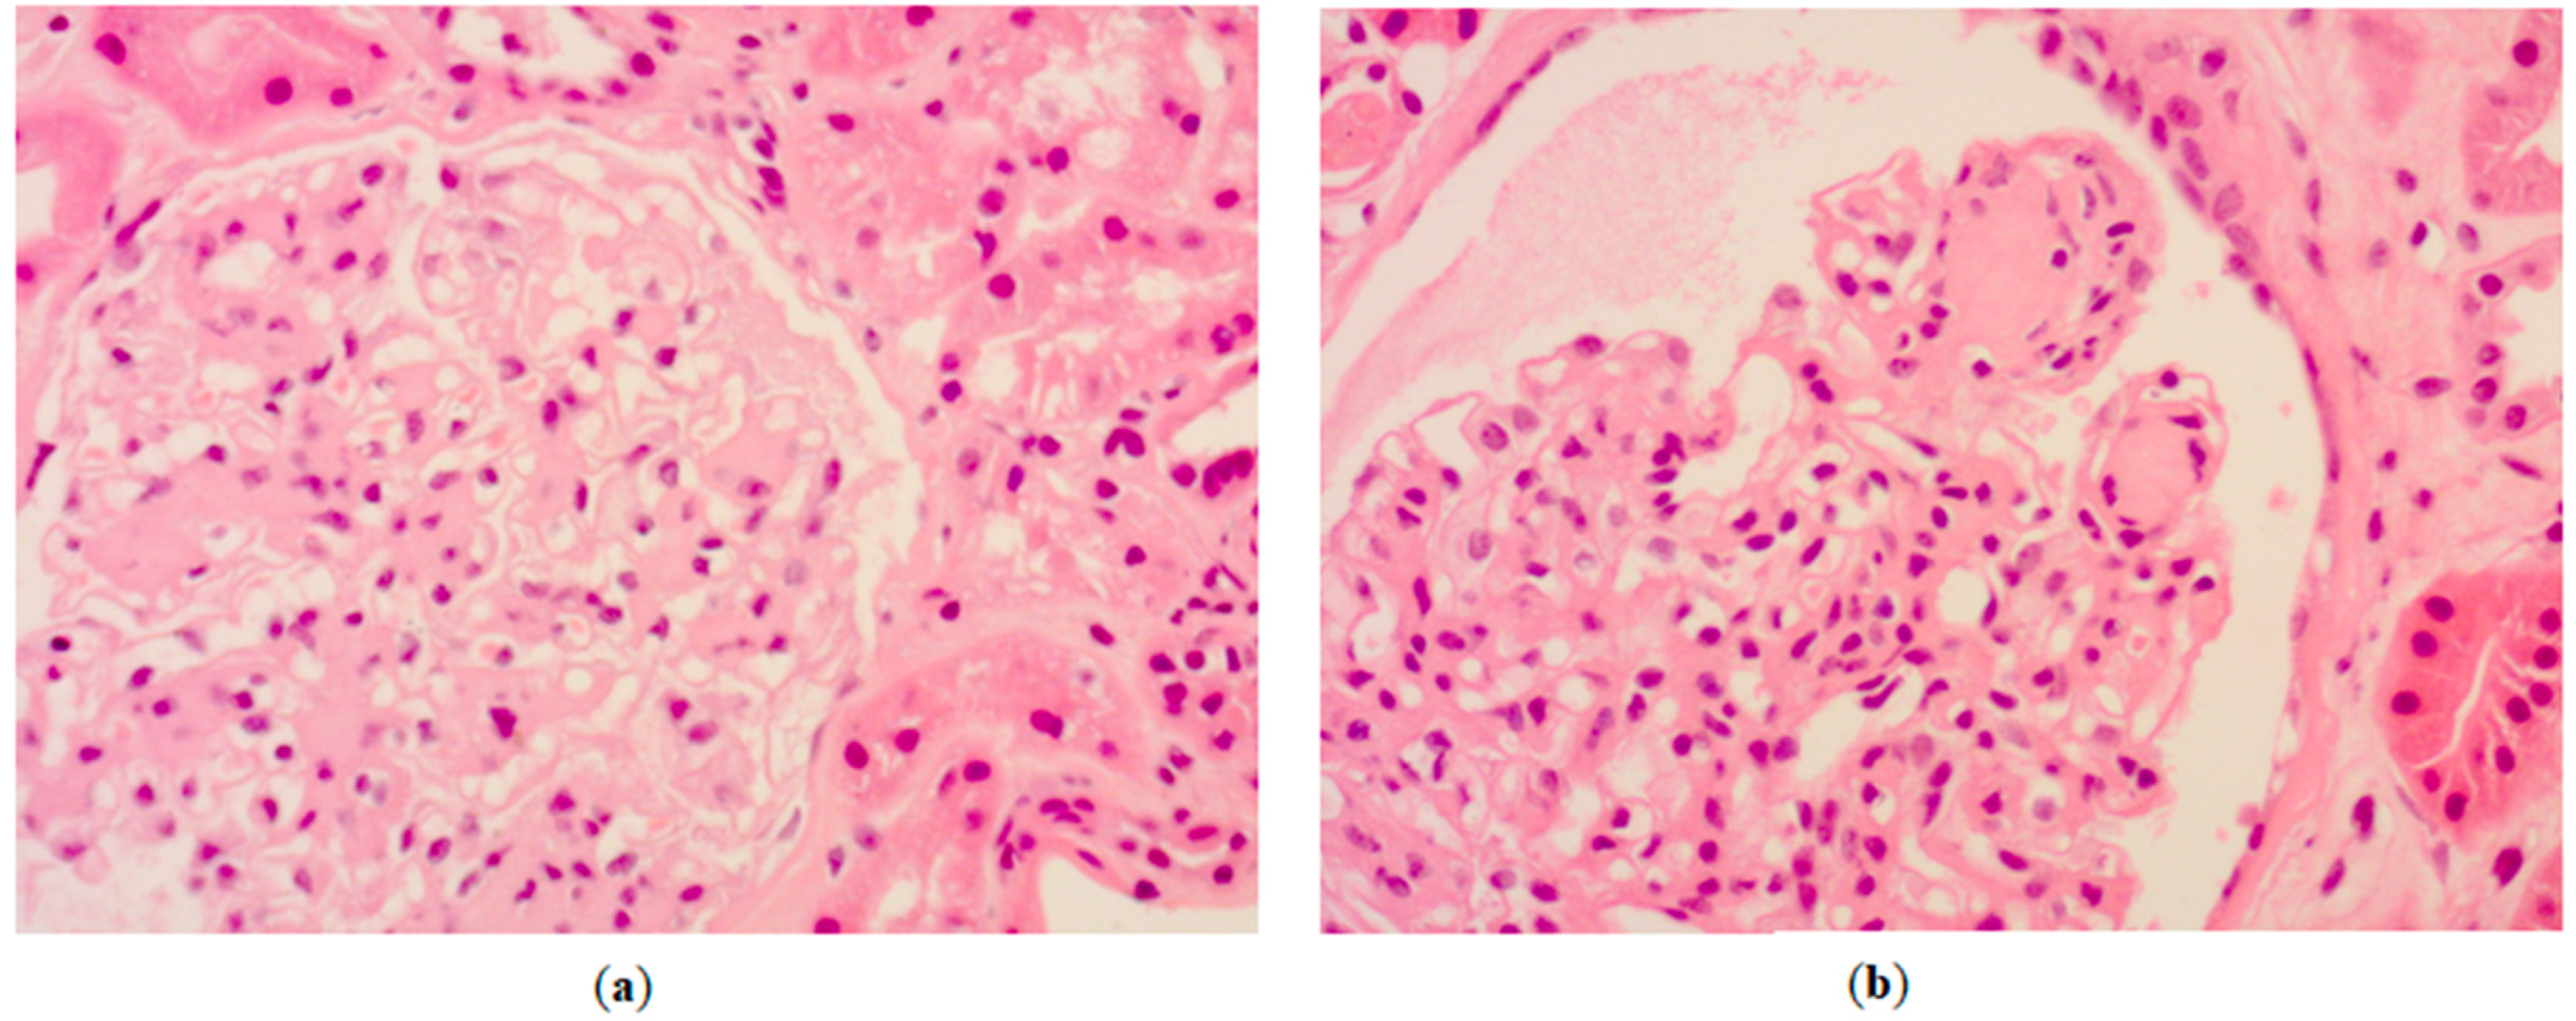

2. Case Report